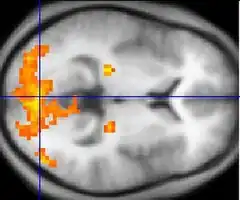

| Functional MRI (fMRI) | Blood-oxygen-level dependent imaging | BOLD | Changes in oxygen saturation-dependent magnetism of hemoglobin reflects tissue activity.[29] | Localizing brain activity from performing an assigned task (e.g. talking, moving fingers) before surgery, also used in research of cognition.[30] | ![]() |

Functional MRI (fMRI) measures signal changes in the brain that are due to changing neural activity. It is used to understand how different parts of the brain respond to external stimuli or passive activity in a resting state, and has applications in behavioral and cognitive research, and in planning neurosurgery of eloquent brain areas.[48][49] Researchers use statistical methods to construct a 3-D parametric map of the brain indicating the regions of the cortex that demonstrate a significant change in activity in response to the task. Compared to anatomical T1W imaging, the brain is scanned at lower spatial resolution but at a higher temporal resolution (typically once every 2–3 seconds). Increases in neural activity cause changes in the MR signal via T*

2 changes;[50] this mechanism is referred to as the BOLD (blood-oxygen-level dependent) effect. Increased neural activity causes an increased demand for oxygen, and the vascular system actually overcompensates for this, increasing the amount of oxygenated hemoglobin relative to deoxygenated hemoglobin. Because deoxygenated hemoglobin attenuates the MR signal, the vascular response leads to a signal increase that is related to the neural activity. The precise nature of the relationship between neural activity and the BOLD signal is a subject of current research. The BOLD effect also allows for the generation of high resolution 3D maps of the venous vasculature within neural tissue.